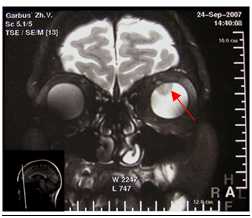

Кроме того, офтальмоскопия позволяет выявить новообразованные сосуды при толщине опухоли 3,5 мм и более. Для их обнаружения на ранних этапах развития меланомы хориоидеи выполняется флуоресцентная ангиография. Этот метод делает доступным для визуализации первые признаки ангиогенеза при толщине новообразования в 1,3 мм. При большом размере опухоли сосуды выглядят толстыми, короткими, с выраженными деформациями структуры, отмечается склонность к образованию хаотической сети. Сосудистые аномалии предрасполагают к развитию кровоизлияний в ткань меланомы хориоидеи и прилежащие структуры глаза, что также можно установить при проведении офтальмоскопического исследования. При ультразвуковом допплеровском цветном картировании выявляются ретинотуморальные шунты. КТ и МРТ осуществляются в предоперационном периоде для точного определения размера и локализации неоплазии, а также для выявления метастазов в другие органы и ткани.

6. КТ\МРТ орбит - бесконтактный метод диагностики, позволяющий в ряде случаев выявить внутриглазное образование, вторичную отслойку сетчатки.